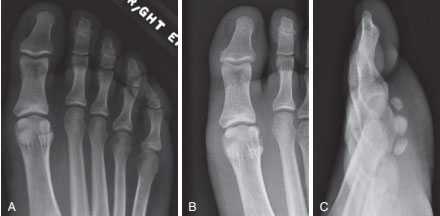

Анатомия 1-го плюснефалангового сустава (ПФС). А, Фронтальный вид. В, Вид изнутри. С, Вид с подошвенной стороны.

Расхождение обеих сесамовидных костей у спортсмена. А, Рентгенограмма до травмы — картина удвоения обеих сесамовидных костей. В, Рентгенограмма после травмы — отмечается расхождение фрагментов обеих сесамовидных костей. С, Рентгенограмма этого же пациента в боковой проекции.